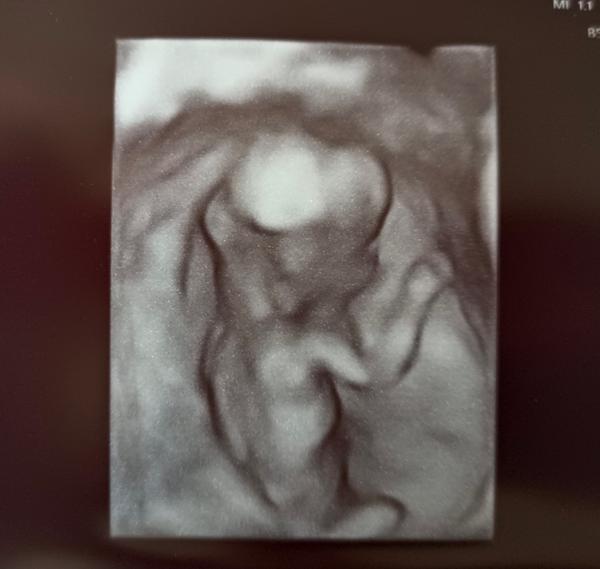

Ahojte 🙂 hlásim sa dnes po kontrole 11+4 presne aj podľa ms aj Utz. Už naozaj verím že to bude všetko dobre 🥹

@zanzilady aaa tak to sa teším 😍 nikdy ma neprestane fascinovať že za pár týždňov sa dokáže vytvoriť takýto človiečik. Držte saaa ❤️

Ahojte žienky, tak ja mám po 1. screeningu a podľa doktora vyzerá byť všetko ok, len je trošičku väčšie, podľa ms 13+1 a podľa uzv 13+3, má 76mm 🙂 k pohlaviu sa nechcel vyjadrovať, tak uvidíme 😅 vrtelo sa veľmi, ako sa vrtí od začiatku tehu 🫣 výsledky z krvi ešte uvidím budúci týždeň v stredu, snáď to bude ok